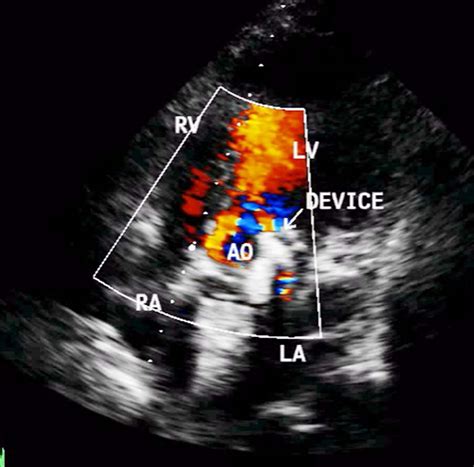

If you experience these symptoms, your doctor will likely recommend an echocardiogram. This is an ultrasound test that creates real-time images of your heart, allowing the cardiologist to see the valves in action, measure the size of the leak, and determine how well your heart muscle is pumping.